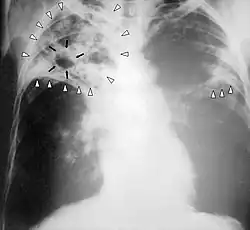

Kommt es bei geschwächten Personen zu einer Aussaat der Mykobakterien über die Blutbahn mit Beteiligung beider Lungenhälften und vieler Organe gleichzeitig, spricht man von einer Miliartuberkulose. Sie ist nach der im Röntgenbild sich darstellenden miliaren (hirsekornartigen, von lateinisch milium „Hirse, Hirsekorn“) Aussaat[36] (Metastasierung) benannt und stellt sich als schweres Krankheitsbild mit erheblicher Beeinträchtigung des Allgemeinzustandes, Fieber, Appetitlosigkeit, Gewichtsverlust, Husten und Luftnot dar. Auch eine Hirnhautentzündung (tuberkulöse Meningitis) kann auf diesem Weg entstehen. Diese zeigt sich zunächst in uncharakteristischen Symptomen wie Irritabilität und Wesensveränderung. Später kann es zu meningitischen Zeichen mit Kopfschmerzen, Nackensteifheit, Halluzinationen, Bewusstseinsstörungen, Krampfanfällen sowie Fieber, also einer schweren Beeinträchtigung des Allgemeinzustandes kommen. Unbehandelt führt sie zu Koma und Tod. Es können, wie Cohnheim schon 1866 festgestellt hat, als Symptom der akuten Miliartuberkulose zudem Tuberkel der Aderhaut (Chorioidaltuberkel) auftreten.[36][37] Bei extremer Abwehrschwäche kann es zu einer fulminanten Sepsis mit in der Regel tödlichem Ausgang kommen, die vielfach als Landouzy-Sepsis bezeichnet wird.

Besteht aufgrund von Symptomen und Vorgeschichte der Verdacht auf eine Tuberkulose, so sind auch bei negativem Tuberkulin-Test die Röntgenuntersuchung oder bei besonderen Fragestellungen die CT der Lunge gut brauchbare bildgebende Untersuchungsverfahren. Sie lassen oft das charakteristische, mottenfraßartige Bild des Lungenbefalls der Tuberkulose erkennen, welches der Erkrankung auch den Beinamen die Motten eingebracht hat. Auch bei geschlossener Tuberkulose zeigen diese Untersuchungen einen Befund. Nachteilig ist aber, dass auf einem Röntgenbild oft nicht ausreichend sicher zwischen einer Tuberkulose und anderen Lungenerkrankungen differenziert werden kann.